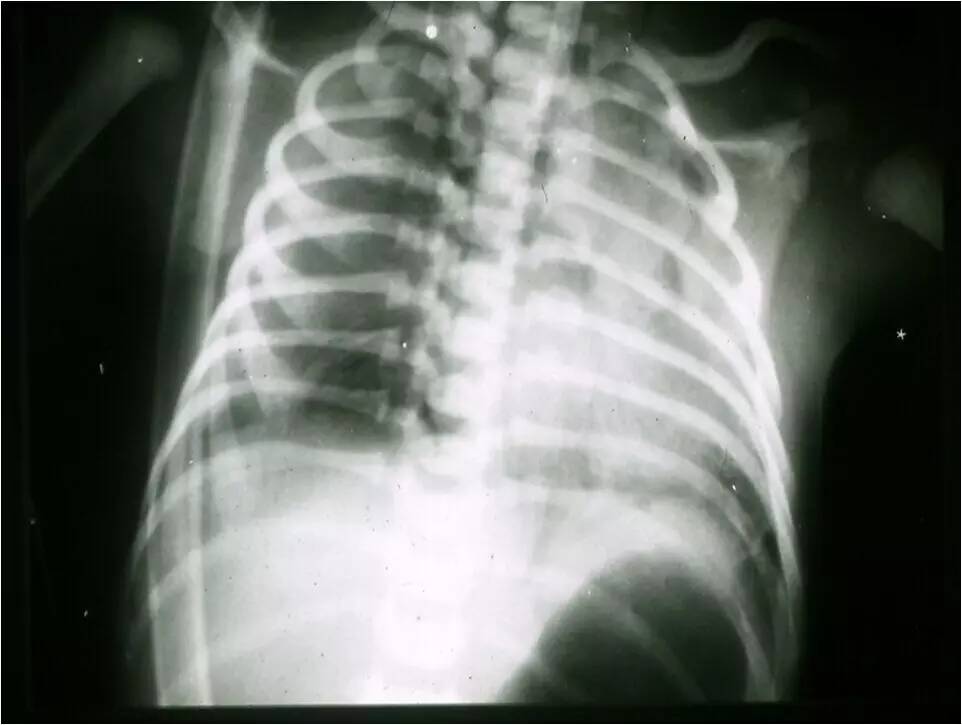

MAS影像学表现

临床特征